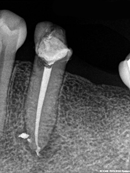

Root Canal Cases